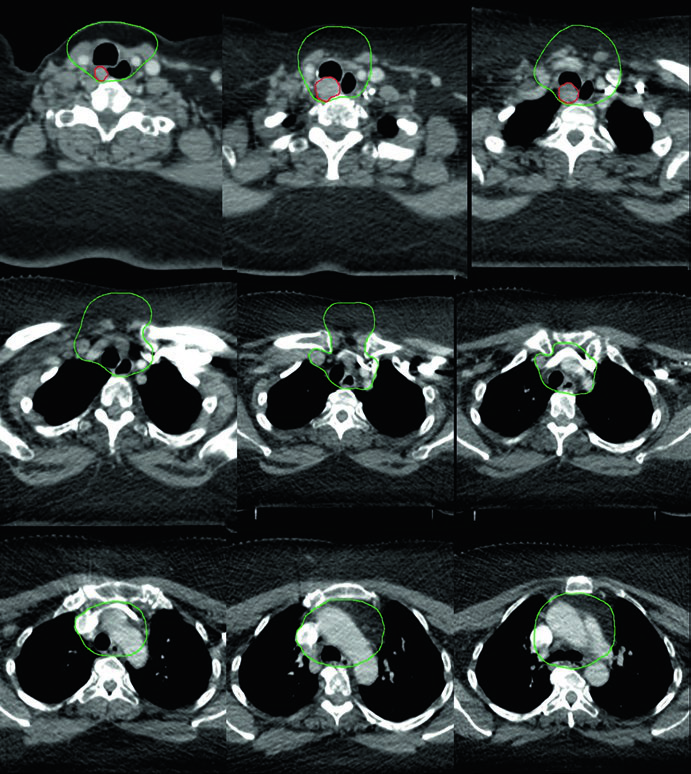

Caso 5 — Câncer pouco diferenciado, fenótipo folicular (Fig. 9.5): Mulher de 69 anos com câncer de tireoide pouco diferenciado de fenótipo folicular, aderido a traqueia e esôfago, submetida a ressecção e iodo radioativo, que recorreu com massa paratraqueal direita invadindo a traqueia. Após nova ressecção e esvaziamento cervical, recebeu quimiorradiação adjuvante. O CTV60 Gy (verde) cobre o compartimento central e o mediastino superior. O tratamento do pescoço lateral foi omitido, dada a alta probabilidade de recorrência no compartimento central — a dose e o risco foram priorizados onde o benefício clínico era máximo.

A decisão de omitir o pescoço lateral não é trivial. Ela pressupõe que o risco de recorrência lateral é suficientemente baixo para que a redução de toxicidade justifique a ausência de cobertura. No cenário deste caso — doença central recorrente com esvaziamento cervical recente e sem linfonodos laterais comprometidos — a omissão é razoável e alinhada com o princípio de individualização do tratamento. Omitir o pescoço lateral reduz significativamente o volume irradiado, com benefício direto na preservação da função de deglutição e redução de xerostomia.